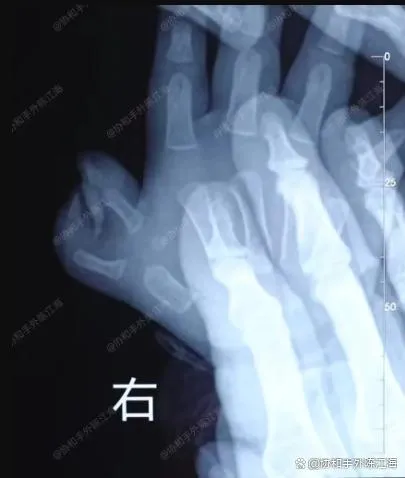

ऑपरेशन से पहले एक्स-रे

यह हैनान प्रांत के एक बच्चे का मामला है, जो उस समय एक वर्ष से अधिक का था। बच्चे के दाहिने हाथ पर पॉलीडेक्टाइली थी। यह दिखने में वैसा ही था जैसा हम आमतौर पर "केकड़ा पंजा" पॉलीडेक्टाइली के रूप में संदर्भित करते हैं, लेकिन बच्चे का मामला काफी अनोखा था। इसका इलाज सामान्य केकड़े के पंजे की सर्जरी विधि से नहीं किया जा सकता था और इसके बजाय इसकी आवश्यकता थी"शीर्ष पर"तकनीक.

उदाहरण के लिए, इस बच्चे के मामले में, परामर्श के दौरान यह स्पष्ट था कि बाहरी अंगूठा अधिक सक्रिय था। माता-पिता ने यह भी देखा कि एक तरफ "मजबूत" था, जबकि दूसरी तरफ "बेहतर दिख रहा था।"